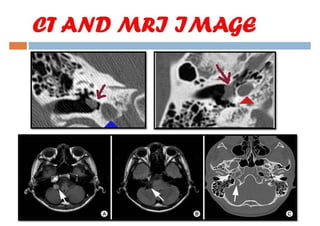

Glomus tumor

A Presentation on the various Glomus tumors of the ear and their treatment Modalities.